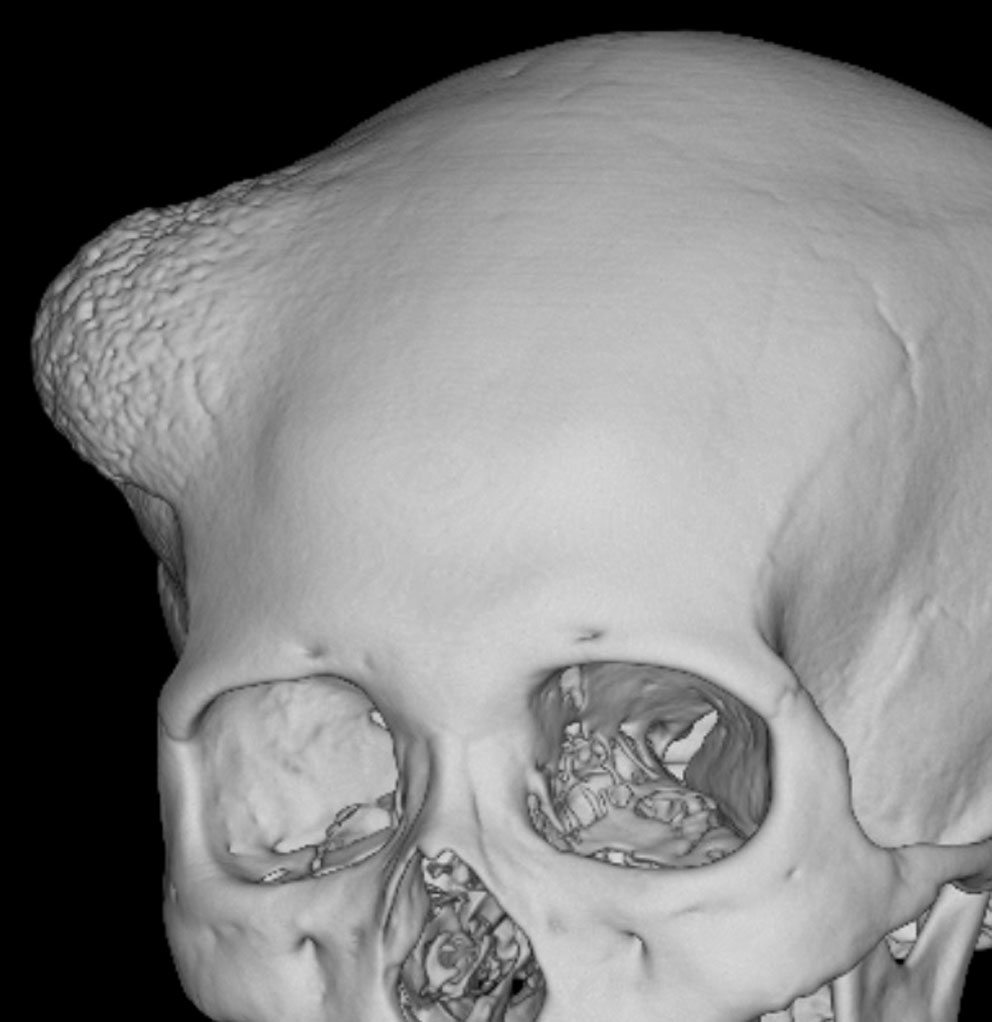

骨内増殖をする髄膜腫です。頭蓋骨腫瘍と間違えるようなものです。触った感じは骨腫ですが,CTでは,表面が毛羽立っていて,頭蓋冠に浸潤していることが特徴です。浅側頭動脈からの豊富な血流があります。

わずかですが頭蓋内にも腫瘍があり,硬膜が肥厚してガドリニウム増強されます。

頭蓋骨をかなり広範におかすので骨は捨てません。開頭して取り外した骨の厚くなっている部分と髄膜腫で軟らかくなっている部分を削除して,それから骨片をオートクレーブで短時間熱処理して,元あった所にもどします。下の画像は手術後1年半が経過したものですが,髄膜腫の再発はなく,熱処理骨弁は吸収されないで生着しています。